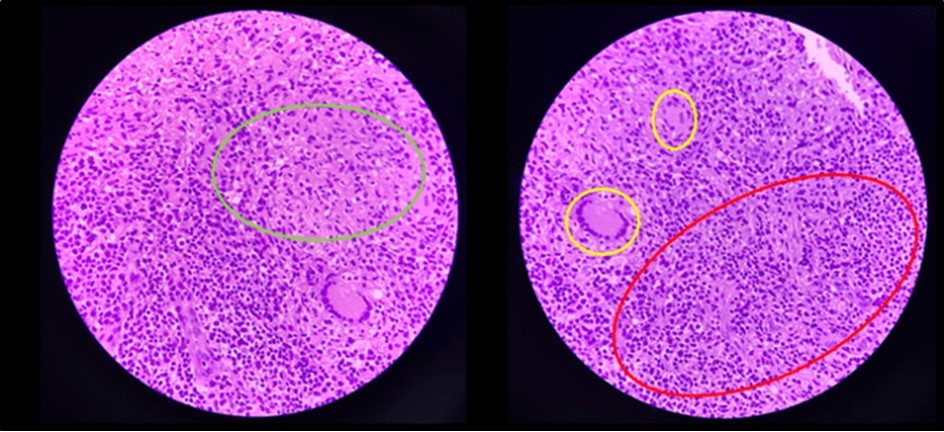

Figure 7.Pathologic slide in the high power field. Inside the green circle is the epitheloid histiocytes. The yellow circles are the Langhan’s type multinucleated gian cells. And inside the red circle is the lymphocytic infiltrates. Which is suggestive of tuberculous etiology.